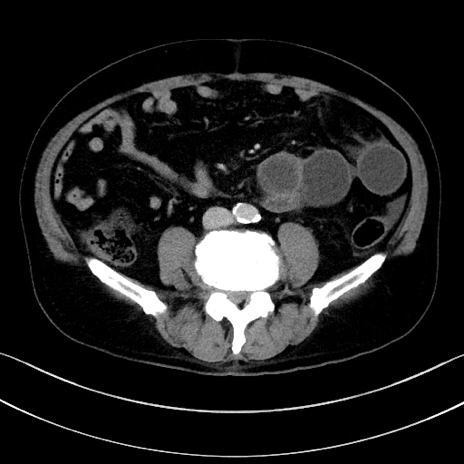

症例15(横断像)

【症例】70歳代男性

【主訴】腹痛

【現病歴】今朝から腹痛あり。全体的に痛い。特に左上の方。排ガスが今日はない。冷や汗が出る。

【既往歴】直腸癌術後

【身体所見】左側腹部〜上腹部に圧痛あり。腹膜刺激症状明らかなではない。軽度反跳痛。左下腹部に術後瘢痕あり。

【データ】WBC 7700、CRP 0.02